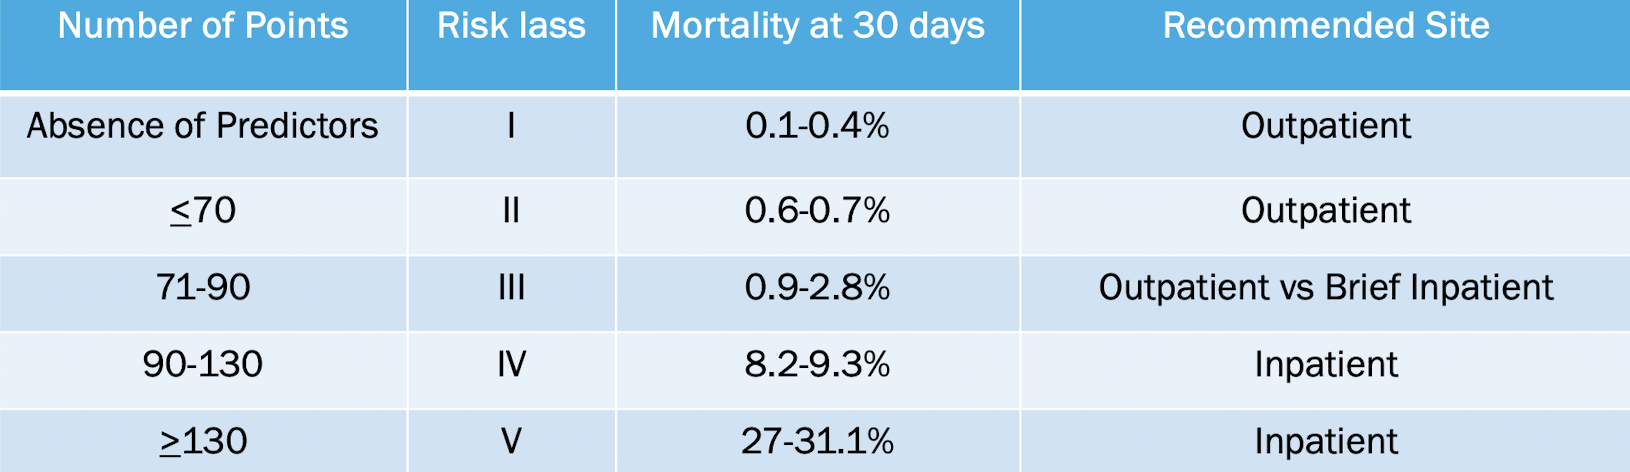

what is pneumonia severity index (PSI)?

guides clinical decision making using specific criteria to risk stratify pts into 1 of 5 classes for 30 day mortality

what is CURB-65?

score is based on 5 easily measurable factors to assess 30 day mortality in risk assessment of CAP

confusion

uremia: BUN > 20

respiration: RR > 30

BP < 90/60

age > 65